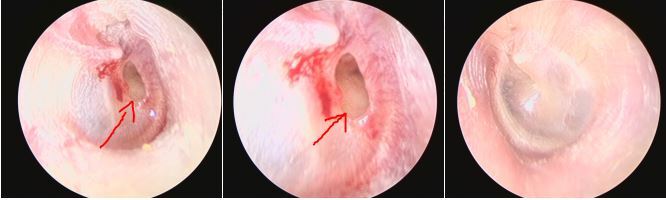

最近遇到一些關(guān)于鼓膜穿孔的爭(zhēng)論,醫(yī)患的角度不同,理解不同,醫(yī)生可以很理性,而患者牽涉自身,往往很感性。非常理解,但是知識(shí)相通才可以構(gòu)建交流的橋梁。所以,關(guān)于鼓膜穿孔這件事兒,想給大家普及一點(diǎn)知識(shí),以便大家可以理性健康的對(duì)待我們的耳朵??耳從解剖角度分外耳、中耳及內(nèi)耳,鼓膜位于外耳道底部,與外耳道有一個(gè)大約45度的夾角,鼓膜的主要作用是聲波傳導(dǎo)作用,由于鼓膜的解剖位置及外耳道與中耳腔微生物環(huán)境的不同,鼓膜也有分界外中耳,起到楚河漢界的作用。最常見的鼓膜穿孔的因素有兩類,一類是耳外傷,另一類是急性炎癥。耳外傷常見的有不良挖耳習(xí)慣損傷,比如掏耳朵不慎棉簽捅入鼓膜導(dǎo)致?lián)p傷,此外,還有打架耳光損傷以及一些重大交通事故損傷。另一類導(dǎo)致鼓膜穿孔的因素多為感染,急性上呼吸道感染后引發(fā)急性中耳炎,耳痛劇烈,流膿,流膿后耳痛減輕。尤其是在兒童期,夜間發(fā)熱、耳痛,急診檢查鼓膜充血紅腫,用藥一兩天發(fā)現(xiàn)耳道內(nèi)多量血性分泌物,大多為急性炎癥刺激導(dǎo)致鼓膜穿孔,檢查可以見到鼓膜表面有光點(diǎn)波動(dòng)—俗稱燈塔征,是中耳膿性分泌外涌的表現(xiàn)。亦有部分反復(fù)發(fā)作的慢性外耳道炎患者,多有不良掏耳習(xí)慣,反復(fù)挖耳或者清理沖洗,炎癥初始分布外耳道,后進(jìn)一步波及鼓膜,導(dǎo)致鼓膜表面有炎癥滲出及肉芽生長(zhǎng),鼓膜菲薄,外力作用或炎癥進(jìn)一步刺激,可導(dǎo)致鼓膜穿孔。鼓膜的生理作用為傳音、分界外中耳的作用,當(dāng)發(fā)生鼓膜穿孔后,鼓膜的傳音作用受到影響,故而多數(shù)穿孔患者都有一定程度的聽力損失。國(guó)內(nèi)外學(xué)者的研究顯示:穿孔越大,聽力損失越重。大部分鼓膜穿孔都有25-40分貝左右的聽力損失,當(dāng)然,鼓膜穿孔導(dǎo)致的聽力下降,也與中耳容積及中耳粘膜的狀態(tài)有關(guān)系。此外,由于外中耳的楚河漢界被破壞,外耳道與中耳腔相通,外源性的感染因素可以直接進(jìn)入中耳,導(dǎo)致中耳炎的發(fā)生。同時(shí),中耳腔被覆粘膜組織,而外耳道是上皮為主,兩者在酸堿度及濕度上均有不同,外中耳交通,易導(dǎo)致外耳道炎癥的發(fā)生。外傷因素導(dǎo)致的鼓膜穿孔,多為裂隙狀、不規(guī)則形穿孔,治療上要求患者保持外耳干燥、禁用滴耳液,適當(dāng)抗炎預(yù)防感染,大多數(shù)外傷性鼓膜穿孔多在兩周到一個(gè)月左右愈合,如果超過三個(gè)月沒有愈合,考慮外傷性鼓膜穿孔無法自愈,就需要進(jìn)一步手術(shù)干預(yù)。穿孔的愈合過程為鼓膜表面上皮向?qū)?cè)爬行的過程,最終會(huì)使不規(guī)則形狀的穿孔愈合。上皮爬行過程可使鼓膜穿孔相鄰邊緣愈合,上皮進(jìn)一步向內(nèi)側(cè)爬行,由不規(guī)則的穿孔,變?yōu)閳A形、橢圓形、腎形或者馬蹄形。故而,慢性反復(fù)發(fā)作的中耳炎,多難自愈,其穿孔也多為近圓形、橢圓形或腎形的。穿孔的病理狀態(tài)存在,使中耳腔不定期處于感染狀態(tài),或有反復(fù)流膿的,也有炎癥過度反應(yīng),使鼓室內(nèi)粘膜玻璃樣變性,進(jìn)而進(jìn)一步導(dǎo)致聽力下降,這就是中耳炎最常見的并發(fā)癥--鼓室硬化。故而,對(duì)于鼓膜穿孔的患者,建議患者選擇合適的時(shí)機(jī),行手術(shù)修補(bǔ)。

最近來自佛山的曾女士找到耳鼻喉鄭立崗醫(yī)生,1天前她去采耳后出現(xiàn)右耳痛,耳堵塞感,聽力下降,耳膜。我檢查檢查后發(fā)現(xiàn)右側(cè)鼓膜穿孔了,估計(jì)是采耳的時(shí)候由于技師的操作不熟練導(dǎo)致的。做了耳內(nèi)鏡檢查后發(fā)現(xiàn)確實(shí)是右側(cè)鼓膜中等大小的穿孔,這種情況需要先觀察看看,如果自己能長(zhǎng)好那是最好的情況。如果觀察一段時(shí)間好不了就需要做耳內(nèi)鏡微創(chuàng)手術(shù)了。對(duì)于采耳的問題,耳鼻喉鄭立崗醫(yī)生一直建議大家對(duì)耳朵的最好保護(hù)就是盡量的不要掏耳朵。能不采耳盡量的還是不要采耳,如果耳朵堵塞發(fā)炎了,還是首選來耳鼻喉科做個(gè)耳內(nèi)鏡要更加的安全一些。關(guān)于鼓膜穿孔,如果您還有什么問題,歡迎留言和耳鼻喉鄭立崗醫(yī)生進(jìn)一步交流。

最近來自廣東潮州的吳先生找到耳鼻喉鄭立崗醫(yī)生要求治療自己的中耳炎鼓膜穿孔。但是陳先生的情況非常特殊,雙側(cè)外耳道先天性狹窄,手術(shù)操作的空間過于狹窄,按正常的手術(shù)步驟是做不了的。入院完善檢查后,耳鼻喉鄭立崗醫(yī)生考慮耳內(nèi)鏡中耳炎微創(chuàng)手術(shù)可以做但是要先在耳內(nèi)鏡下擴(kuò)大外耳道后再修補(bǔ)鼓膜,要不然手術(shù)無法做。制定好方案后就開始了手術(shù),插管全麻后先在耳內(nèi)鏡下用電鉆磨除多余的骨質(zhì),擴(kuò)大外耳道,然后翻起皮瓣,取耳屏軟骨修補(bǔ)鼓膜,整個(gè)的手術(shù)用時(shí)約90分鐘,非常的難做。術(shù)后查房患者無明顯的不適,無面癱等并發(fā)癥。對(duì)于外耳道狹窄的中耳炎鼓膜穿孔的患者,耳內(nèi)鏡下擴(kuò)大外耳道是修補(bǔ)鼓膜的必要步驟。對(duì)于中耳炎微創(chuàng)手術(shù),如果您還有問題,歡迎留言和耳鼻喉鄭立崗醫(yī)生進(jìn)一步交流。